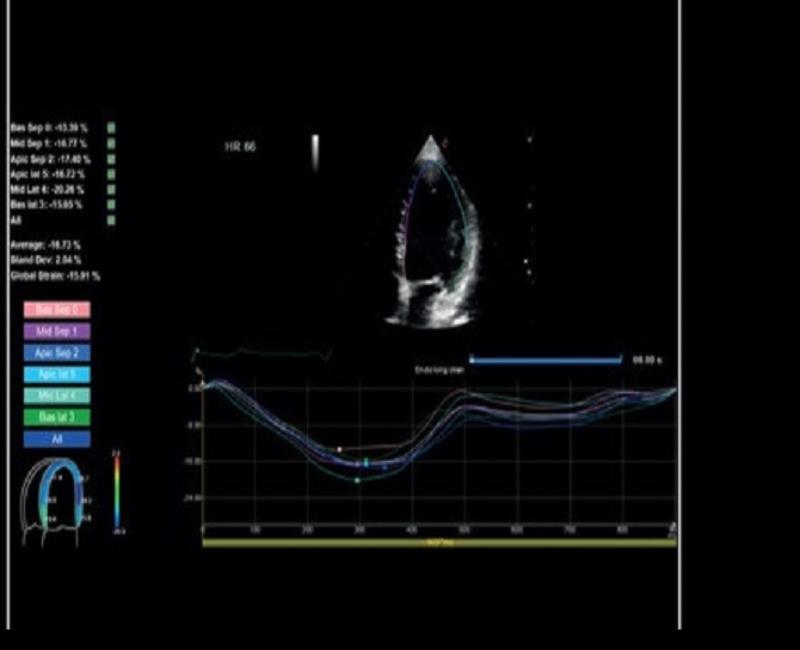

XStrain - Đánh giá vận động vùng tâm thất trái toàn diện với Siêu âm đánh dấu mô cơ tim.

may sieu am mylab x6